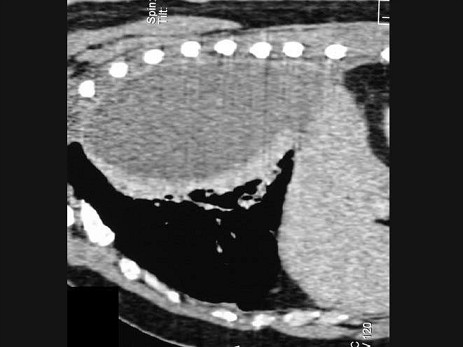

男,59岁,呼吸困难,胸痛,有发热,结合CT图像,最可能的诊断是()

A.脓胸

B.肺脓肿

C.大叶性肺炎

D.肺囊虫病

E.肺癌